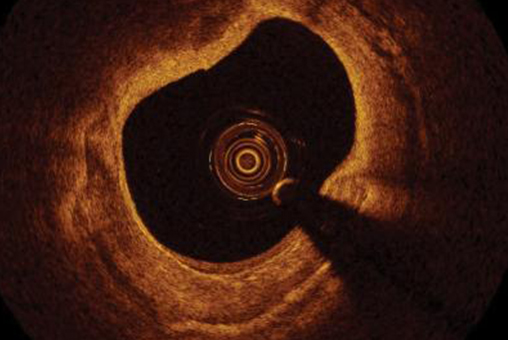

Intravascular Optical Coherence Tomography

Optical coherence tomography (OCT) is a high-resolution imaging modality that uses backscattered light to produce cross-sectional images of biological tissue with micrometer resolution